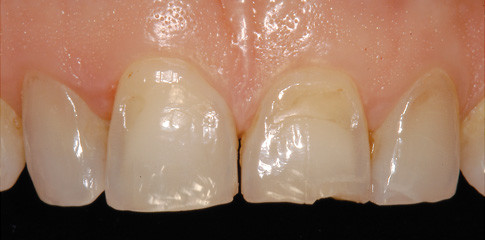

Achtung, erosiv!

Unsere Zähne im Schussfeld der Säuren